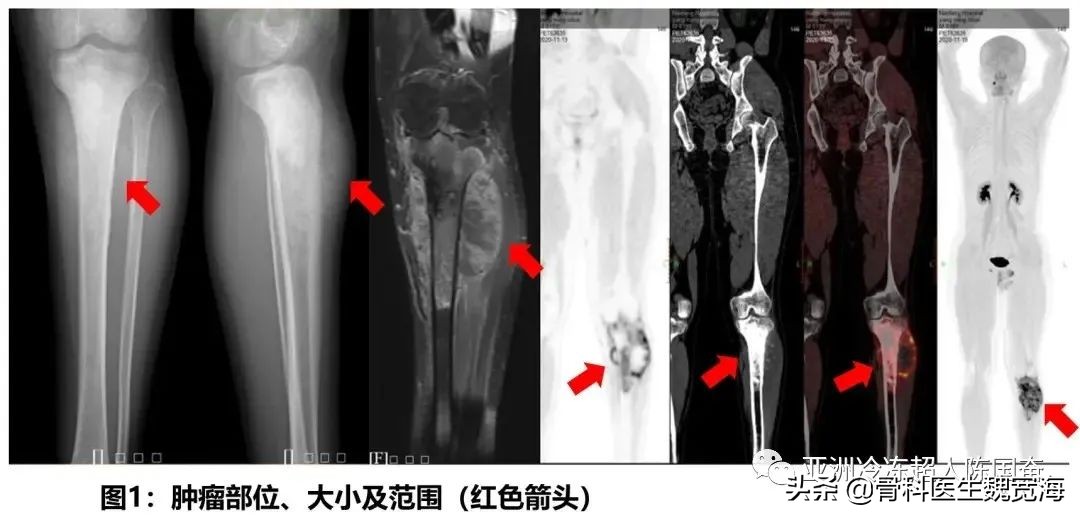

患者是一名19岁的大男孩。左腿痛到南方医院骨科看病时,X光显示肿瘤已经累及了左侧胫骨超过一半的长度。尤其特别困难的是,胫骨的关节面也受累了,这在骨肉瘤中是不多见的。这种情况下,截肢是一种常规的选择。但是患者本人和妈妈都希望尽全力不截肢。经过和家属的充分沟通,医生制定了新辅助化疗+手术+术后化疗的标准治疗方案。 术前两周期新辅助化疗后,经过一周的精心准备,在南方医院创伤骨科余斌主任的亲自指导下,骨肿瘤亚专业组按计划实施了“左胫骨骨肉瘤瘤段切除+液氮冷冻灭活+瘤段回植+肿瘤型膝关节假体置换+胫骨内外侧双钢板内固定术”。手术经历了八个小时的连续奋战,顺利完成。术后20天,患者顺利出院。将进入下一步的综合治疗。